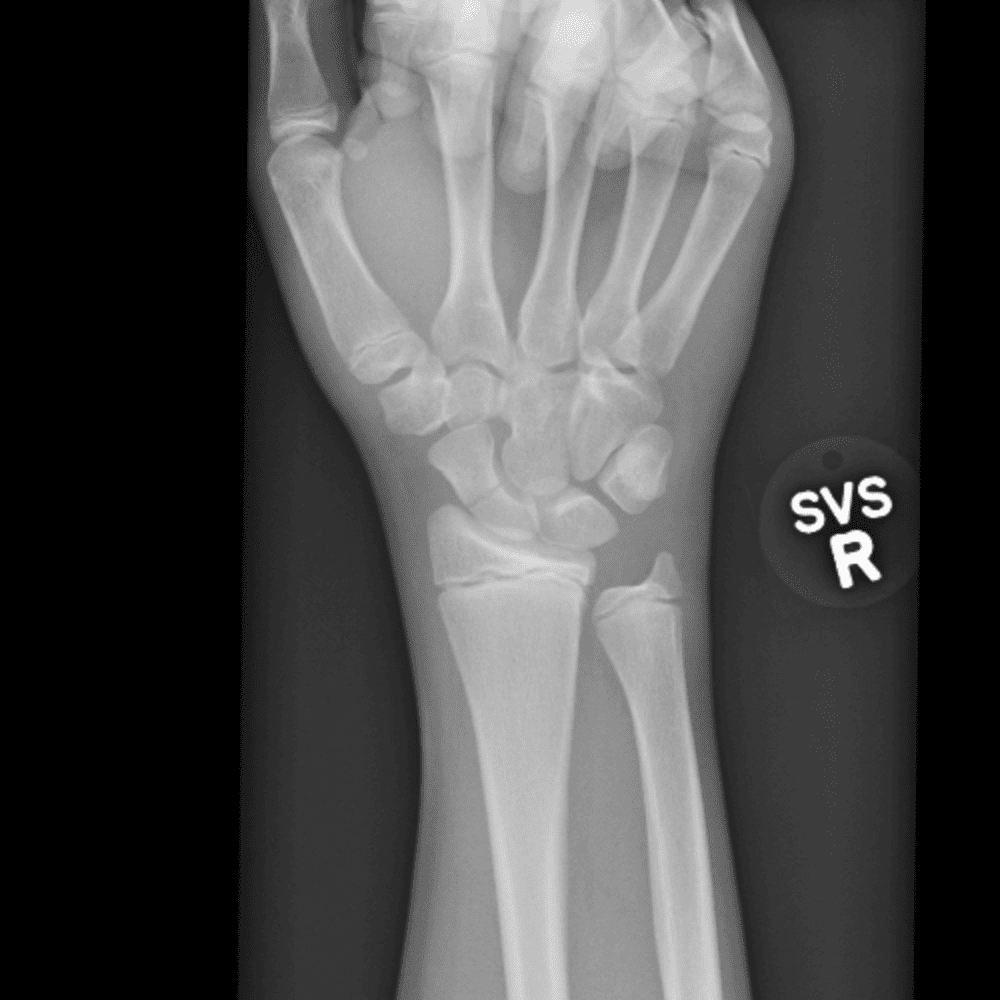

Simulates call by including subtle or difficult cases and some normals.

30 cases